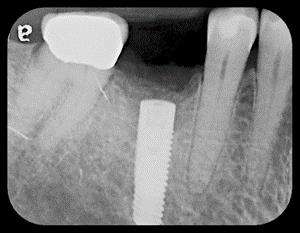

When an implant loses bone on multiple surfaces, it continues to fail and creates a large defect. Ms. R presented with a failing implant having several millimeters of bone loss around it (Fig. 1). The abutment and crown were removed and stored. The implant was detoxified, then grafted with growth-factor-enhanced bone (Fig. 2). After four months, the graft matured and the abutment and crown were reseated (Fig. 3 & 4). Six years later, the bone remains intact around the implant (Fig. 5).

Fig. 1: Failing Implant with Bone Loss Around It